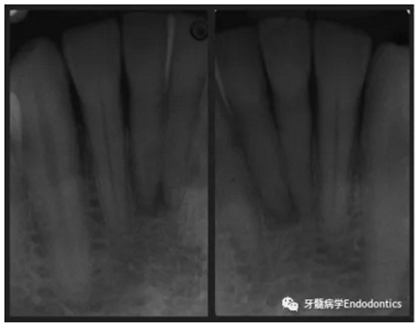

31、41叩痛明顯,牙冠變色(圖1)。溫度和牙髓電活力測試無反應。兩張從不同角度拍攝的x線片顯示,相對于側切牙,雙側下中切牙都有嚴重的根管鈣化(圖2)。41有明顯根尖周暗影,31根尖周暗影不明顯。為進一步證實31是否存在根尖周病變,同時精細觀察31、41的復雜結構,根據歐洲牙髓病學會CBCT應用指南(2014),對患牙拍攝小視野、高分辨率CBCT。CBCT影像證實31、41均伴有根尖周炎和嚴重的根管鈣化(圖3)。距離根尖4mm可見根管影像。 由于患牙根管解剖結構較為復雜,筆者決定使用特殊設計的微型鉆頭(直徑0.85mm)進行“數字化導航牙髓治療”。 因此對下頜進行口內掃描(圖4)。用coDiagnostixTM軟件(Dental Wings Inc.,Montreal,Canada)將CBCT和口內掃描的數據進行處理,該軟件主要用于引導種植。通過該軟件對兩個掃描圖像進行疊加后,虛擬鉆頭尖端沿牙長軸對準根管下段可見部分(圖5)。三維檢查虛擬鉆的正確位置。

圖2. 31、41X線影像。

圖3.下頜前牙CBCT影像。